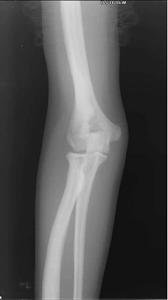

可以無症狀。有些病人身材矯小,發育延遲,容易發生骨折,且癒合緩慢。但不發生畸形連線,這與成骨不全症不同。顱骨硬化,致腦積水及顱神經受壓,導致眼萎縮、面癱、失聽等。副鼻竇腔隙變少,閉塞、引流不暢而致副鼻竇炎。貧血約占30%,重者可以致命,常伴有代嘗性脾、肝及淋巴結腫大。易發生齲齒,導致下頜骨骨髓炎。有些病人可見雞胸及串珠肋。X線表現特徵為骨骼濃厚緻密,失去其原有結構,無法區分皮質及髓腔,兩端膨大呈杵狀。有的患嬰在子宮內已有如此表現。全身大多數骨均可累及,但下頜骨少見。由於骨硬化過程可以變緩或暫停,因此,在骨骼上可見到有深淺不同的橫紋。骨骺亦緻密,有時可見呈同心圓狀。椎體的上、下兩端緻密,但中間有一條骨質正常的帶,常被形容為“夾心麵包椎體”。顱骨亦硬化,氣竇消失,垂體窩變淺,鞍背突增生,顱窩變狹,顱孔縮小。

本病突出的x線改變為廣泛性骨硬化,骨呈無結構的密度增高,骨小梁影像消失,可累及全身或大部骨骼。其易發部位為脊柱、骨盆、肋骨、顱骨、脛腓骨及手足的短管狀骨。患者骨密度顯著增加,皮質增厚,髓腔變窄甚至閉塞。病變呈對稱性分布,小兒期即可顯示病變,重者未出生前子宮內即可發現。

(4)長骨:病變起始於乾骺端,漸向骨幹發展。常可見到深淺交替的波浪狀橫紋。同樣病變也可見於掌、跖、指、趾諸骨,在靠近骨骺一端較為明顯。

X線表現:基本X線表現廣泛均勻,骨密度增高硬化,骨小梁變粗、模糊,皮質增厚,髓腔狹窄,甚至消失。本院曾有3例石骨症病人,因發生骨折,欲行帶鎖髓內針固定,因髓腔消失,骨質硬化,改用鋼板或動力髁鋼板固定,骨密度增高有明顯的均勻對稱性,以四肢、肋骨和骨盆較明顯。骨中骨主要見於掌指、跖趾關節及肋骨等,骨中骨表現為邊界比較明顯的緻密骨島。夾心椎又名夾心蛋糕征,其形成是由於椎體上下軟骨板富含血管,在鈣吸收不足的情況,該部類骨質沉積過多。類骨質對破骨細胞具有明顯的抑制作用,而椎體中部缺乏這種類骨質,故而被破骨細胞侵蝕,形成椎上下高密度而中間低密度,形如三明治樣。髂骨翼年輪樣改變。射線可透過帶是較正常骨區域,而緻密帶存在大量不起作用的破骨細胞。顱骨穹窿顱底均增厚硬化,以顱底骨質增生最明顯。

本病X線表現具有特徵性,其特徵為骨骼濃厚緻密,失去其原有結構,無法區分皮質及髓腔,兩端膨大呈杵狀。有的患嬰在子宮內已有如此表現。全身大多數骨均可累及,但下頜骨少見。由於骨硬化過程可以變緩或暫停,因此,在骨骼上可見到有深淺不同的橫紋。骨骺亦緻密,有時可見呈同心圓狀。椎體的上、下兩端緻密,但中間有一條骨質正常的帶,常被形容為“夾心麵包椎體”。顱骨亦硬化,氣竇消失,垂體窩變淺,鞍背突增生,顱窩變狹,顱孔縮小。

石骨症為全身性骨骼受累的疾病,顱骨的X線表現為硬化,尤以顱底為顯著,特別是蝶骨體及大、小翼均明顯改變。蝶鞍大小正常或縮小,床突、鞍底皆硬化。顳骨及枕骨也可硬化,使板障封閉,失去三層的分野。頂骨額骨及顏面骨可不受侵犯或僅有輕微變化。視神經孔變窄且邊緣模糊乳突小房及鼻旁竇變小或發育不全石骨症在長管狀骨及脊椎有特徵性的X線改變。脊椎椎體表現為上下緣特别致密,其間密度低者為正常骨質,組成三層帶狀影。長管狀骨表現為“骨內骨”,骨質緻密髓腔變窄或消失於乾骺部顯示多條互為平行或呈波狀緻密線紋,乾骺部可呈杵狀變形,尤其脛骨上端內側可表現為邊緣不整呈粗鋸齒改變,髂骨翼典型改變為平行髂嵴,的多層的同心弧狀硬化帶此外,肋骨和鎖骨均可呈均勻硬化。有時還可見到骨折,於掌、蹠、指及趾骨常有界限分明的骨島出現。